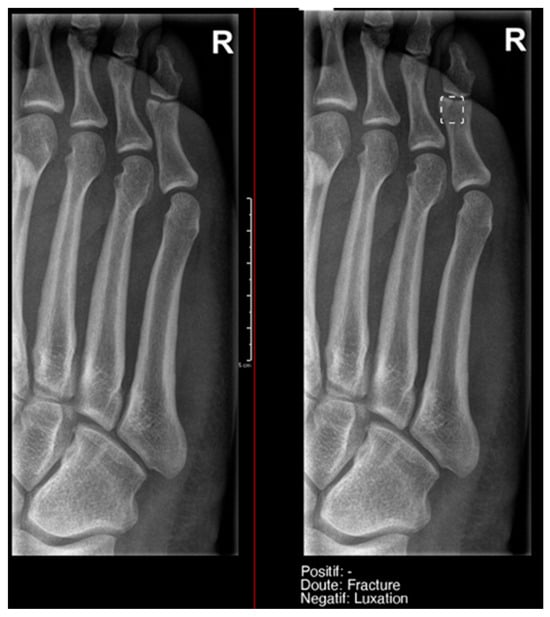

- Ankle and foot: On six occasions, Milvue marked the fracture variable as doubtful in cases with a bipartite medial sesamoid (two patients), an accessory sesamoid at the base of the 5th metatarsal, synphalangism, os peroneum, and os naviculare. (Figure 8).